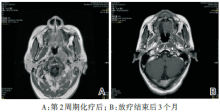

胸部CT(2013-07-31)示: 左肺下叶后基底段见一肿块影, 呈分叶状, 边缘见短毛刺, 后缘见胸膜牵拉征, 周围见少许斑片状模糊影, 增强后肿块较明显不均匀性强化, 其内可见小空泡征, 大小约22 mm× 15 mm。双肺野见多个小圆形结节影, 边界较清楚, 最大者直径约6 mm。诊断:考虑左肺下叶周围型肺癌并少许阻塞性肺炎, 建议穿刺活检; 考虑合并双肺多发转移(见图2)。

图2 胸部CT图像(2013-07-31)

刘辉(放射科主任医师):患者胸部CT可见双肺多发类圆形结节, 主要分布在胸膜下, 考虑转移瘤的可能性较大, 另外可见左下肺后基底段一较大结节, 具有多种恶性征象:肿瘤生长受到血管的阻隔可见明显分叶征, 周边较多短毛刺, 在重建的CT上可见左支气管内有阻断, 并造成了阻塞性炎症, 病变靠近肺门的一侧可见血管纠集征, 薄层扫描可见肿物内有空泡征, 增强像可见肿物增强明显, 增强后的重建可见肿物包绕血管, 血管边界不清, 提示肿物侵犯血管, 综合以上征象, 我们考虑左下肺肿物为肺原发恶性肿瘤。而对于双肺多发转移瘤, 影像学上很难以鉴别是由鼻咽癌还是左下肺肺癌转移而来, 只能从概率来看, 对于肺内转移灶来说, 最多见的原发灶为肺癌, 其次为泌尿生殖道肿瘤。另外, 肺转移瘤可能会拥有原发部位肿瘤的特征, 如有文献报道, 鼻咽癌的肺转移瘤出现空洞坏死, 但只是个案报道无太大参考意义。因此, 我们考虑双肺多发结节为肺癌转移瘤可能性较大。

吴一龙(肿瘤学教授):根据影像学资料考虑双肺散发的结节为转移瘤, 而左下肺肿物为原发性肺癌, 但对于双肺转移瘤的来源判断较困难, 可从原发肿瘤的分期来考虑, 比如鼻咽癌偏晚期, 则考虑鼻咽癌转移瘤可能性大, 反之亦然。而对于这个病例, 肺部原发肿瘤的分期为T1b, 发生对侧转移的可能性较小, 而鼻咽部肿瘤的分期较晚, 发生肺转移的可能性较大。

李伟雄(放疗科主任医师):影像学上难以判断双肺转移瘤的来源, 从临床上分析, 此患者的鼻咽癌分期为T3, 双侧淋巴结虽无明显肿大但呈簇状分布, 考虑淋巴结分期为N2。而鼻咽癌的肺转移概率与淋巴结分期密切相关, 如锁骨上区淋巴结阳性, 分期为N3, 则发生肺转移的概率大大增高。本患者鼻咽癌为局部晚期, 有一定肺转移的可能。另外, 本患者肺内原发肿物较小, 发生对侧肺转移可能性小, 同时, 若发生对侧肺转移, 纵隔一般可见肿大淋巴结, 本患者纵隔无肿大淋巴结, 故考虑肺癌肺转移瘤可能性小。